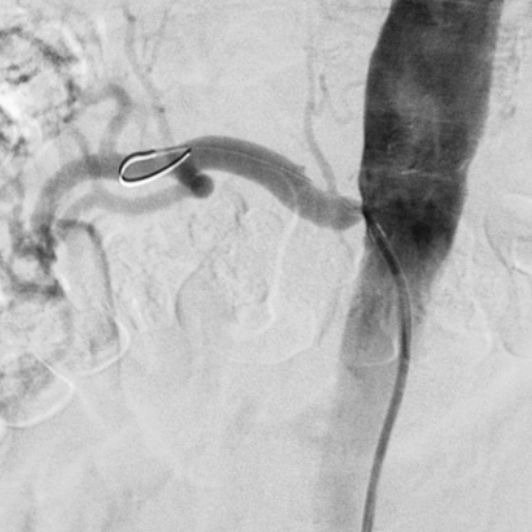

Outcomes observed in patients treated with image-guided, minimally invasive vascular procedures.

Results vary by patient and condition. Images are for educational purposes only.